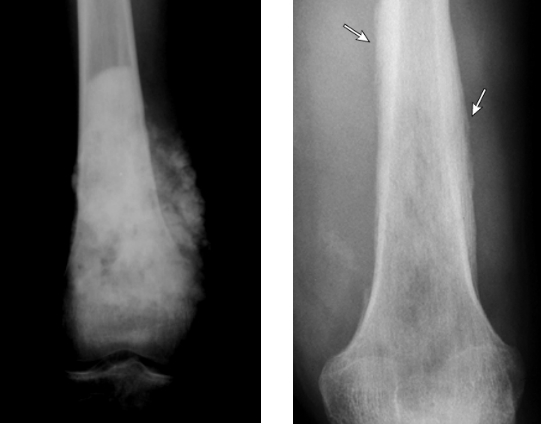

影像学检查(X光片、CT、核磁共振): 这是最直接的“雷达扫描”,三种检查通过互相参考,可以明确评估肿瘤的大小、位置和破坏范围。骨肉瘤和尤文肉瘤在片子上常常可以看到明确的骨质破坏,骨肉瘤可以在X光片上看到Codman三角、日光放射影等等的表现,而尤文肉瘤在X光片上有时会出现像“洋葱皮”一样的特殊表现,这些都是帮助医生发现它们的重要线索。此外,胸部CT扫描在诊断肺转移方面尤其重要,因为肺是骨肉瘤、尤文肉瘤最常见的转移部位。

图2 骨肉瘤和尤文肉瘤的典型X线表现